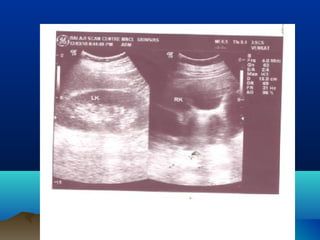

PHYSIOLOGICALPHYSIOLOGICAL

HYDRONEPHROSISHYDRONEPHROSIS

โ€ข RIGHT > LEFT

โ€ข DEXTROROTATION

โ€ข RIGHT OVARIAN VESSELS

โ€ข LEFT โ€“ PROTECTION BY SIGMOID COLON